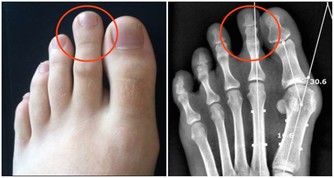

膝關節尤其是人體所有關節、軟骨構造中最為複雜的部位,

包括髕骨、大腿股骨、小腿脛骨、兩個半月狀軟骨及四條韌帶,活動機轉相當複雜。

膝關節

膝關節可以說是退化性關節炎的最大宗。關節就如同車子的輪胎般,如果常煞車、摩擦多,輪胎就會提早報銷。門診中患者常見的主述症狀如下:

⑴疼痛加上軟痠及卡住的感覺,多屬半月軟骨的問題。

⑵下樓梯時膝蓋痠軟,多屬髕骨軟化,以女性居多。

⑶從坐姿站起時兩腿感到痠軟,通常屬於骨小樑退化。

⑷關節感到卡卡的,且無法伸直或彎曲,則是半月板破裂。